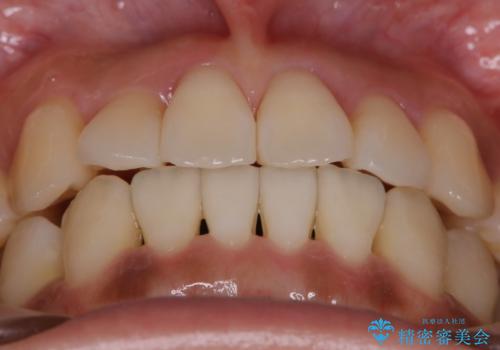

【非抜歯】左右の八重歯・前歯の反対咬合の改善 インビザライン

- 前歯のガタつきを主訴にご来院されました。

診査の結果、骨の厚みに余裕がなく幅の拡大とIPR(歯と歯の間を削り隙間を作る作業)のみでは歯周病に対する不安が残ることが懸念されたため、マイクロインプラントを用いて奥歯から順にすべての歯を後方移動させる方法によってスペースを作ることとなりました。

歯を奥に移動させてスペースを作る方法を用いる場合、マウスピースの装着時間ならびに装着時の適合度がそれぞれ良い状態で保たれているかどうかが大きく関わってきます。

コンプライアンスが遵守されず、使用方法にバラつきがあるとマウスピースを作り直さなければいけなくなる可能性が上がってしまう傾向にあります。